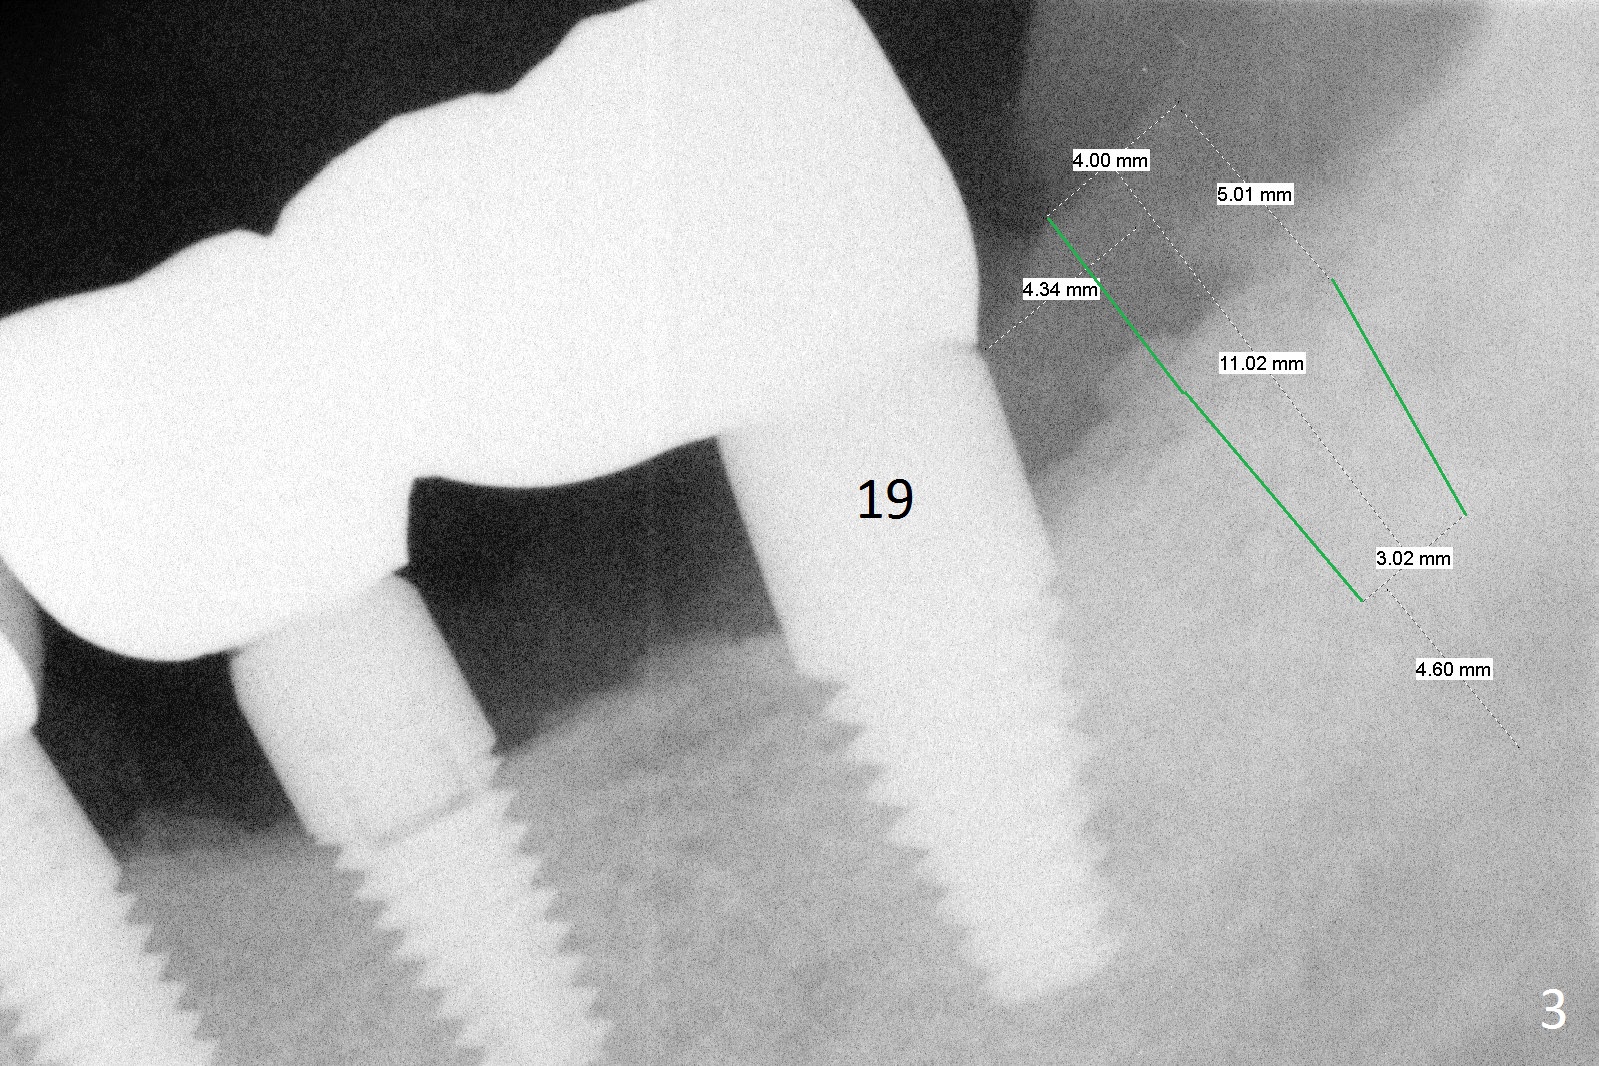

A 58-year-old man has two types of implant complications: periimplantitis at #4 (in spite of 2 bone graft surgeries, Fig.1) and abutment loosening at #14 and repeatedly 19 (probably due to bruxism, Fig.2,3).

To overcome bruxism, implants will be placed at the 2nd molar sites (total 4). Since the implant at #19 was placed distal, the crowns at #18 and 19 will be splinted. The unipost at #14 is 6 mm, 10º cemented with Ketac (implant 8x14 mm). To increase retention, use bonding and place 1 or 2 heavy retention grooves or use a straight abutment. If the existing abutment cannot be removed, enlarge the retention groove and bury a piece of wire in the groove with bonding. The last resort will be splinting with #15.